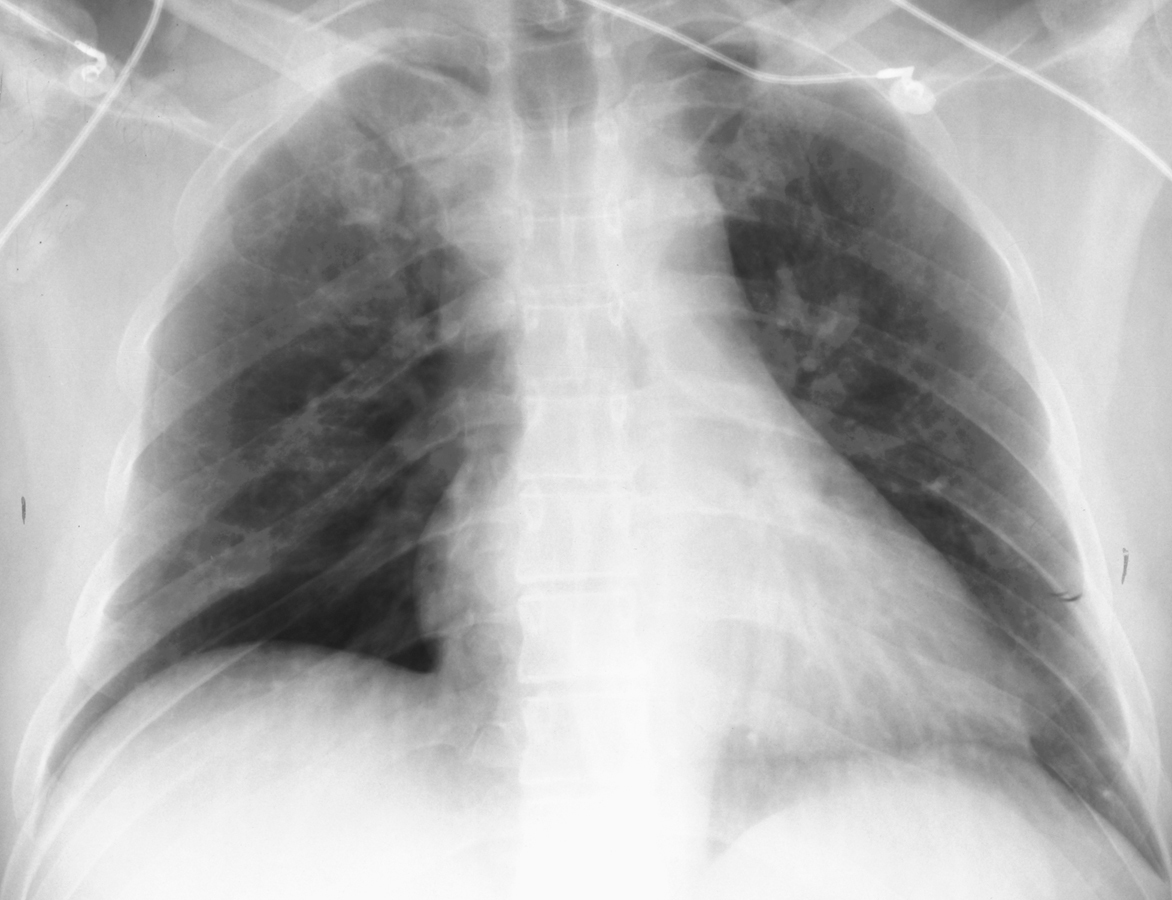

Tension Pneumothorax

Mediastinal shift is usually seen in a tension pneumothorax, but the use of PEEP may prevent this from occurring. The most reliable sign of tension pneumothorax is depression of a hemidiaphragm. Other signs of tension pneumothorax include shifting of the heart border, the superior vena cava, and the inferior vena cava. The shifting of these structures can lead to decreased venous return.